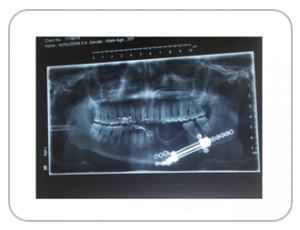

A 35 year old male had a visible defect in the left side of his mandible. Medicad Implants developed and manufactured a customized distractor to aid in Transport Distraction procedure on the patient. The segmented mandible was successfully distracted over a length of 30mm with a satisfactory outcome.

DISTRACTOR DESIGN

X-RAY IMAGE SHOWING DISTRACTOR POST IMPLANTATION